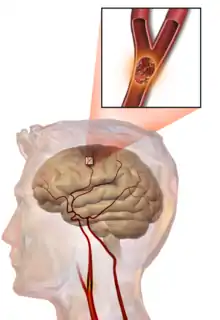

Illustration of an embolic stroke, showing a blockage lodged in a blood vessel.

In thrombotic stroke, a thrombus[39] (blood clot) usually forms around atherosclerotic plaques. Since blockage of the artery is gradual, onset of symptomatic thrombotic strokes is slower than that of a hemorrhagic stroke. A thrombus itself (even if it does not completely block the blood vessel) can lead to an embolic stroke (see below) if the thrombus breaks off and travels in the bloodstream, at which point it is called an embolus. Two types of thrombosis can cause stroke:

An embolic stroke refers to an arterial embolism (a blockage of an artery) by an embolus, a traveling particle or debris in the arterial bloodstream originating from elsewhere. An embolus is most frequently a thrombus, but it can also be a number of other substances including fat (e.g., from bone marrow in a broken bone), air, cancer cells or clumps of bacteria (usually from infectious endocarditis).[45]

Because an embolus arises from elsewhere, local therapy solves the problem only temporarily. Thus, the source of the embolus must be identified. Because the embolic blockage is sudden in onset, symptoms usually are maximal at the start. Also, symptoms may be transient as the embolus is partially resorbed and moves to a different location or dissipates altogether.